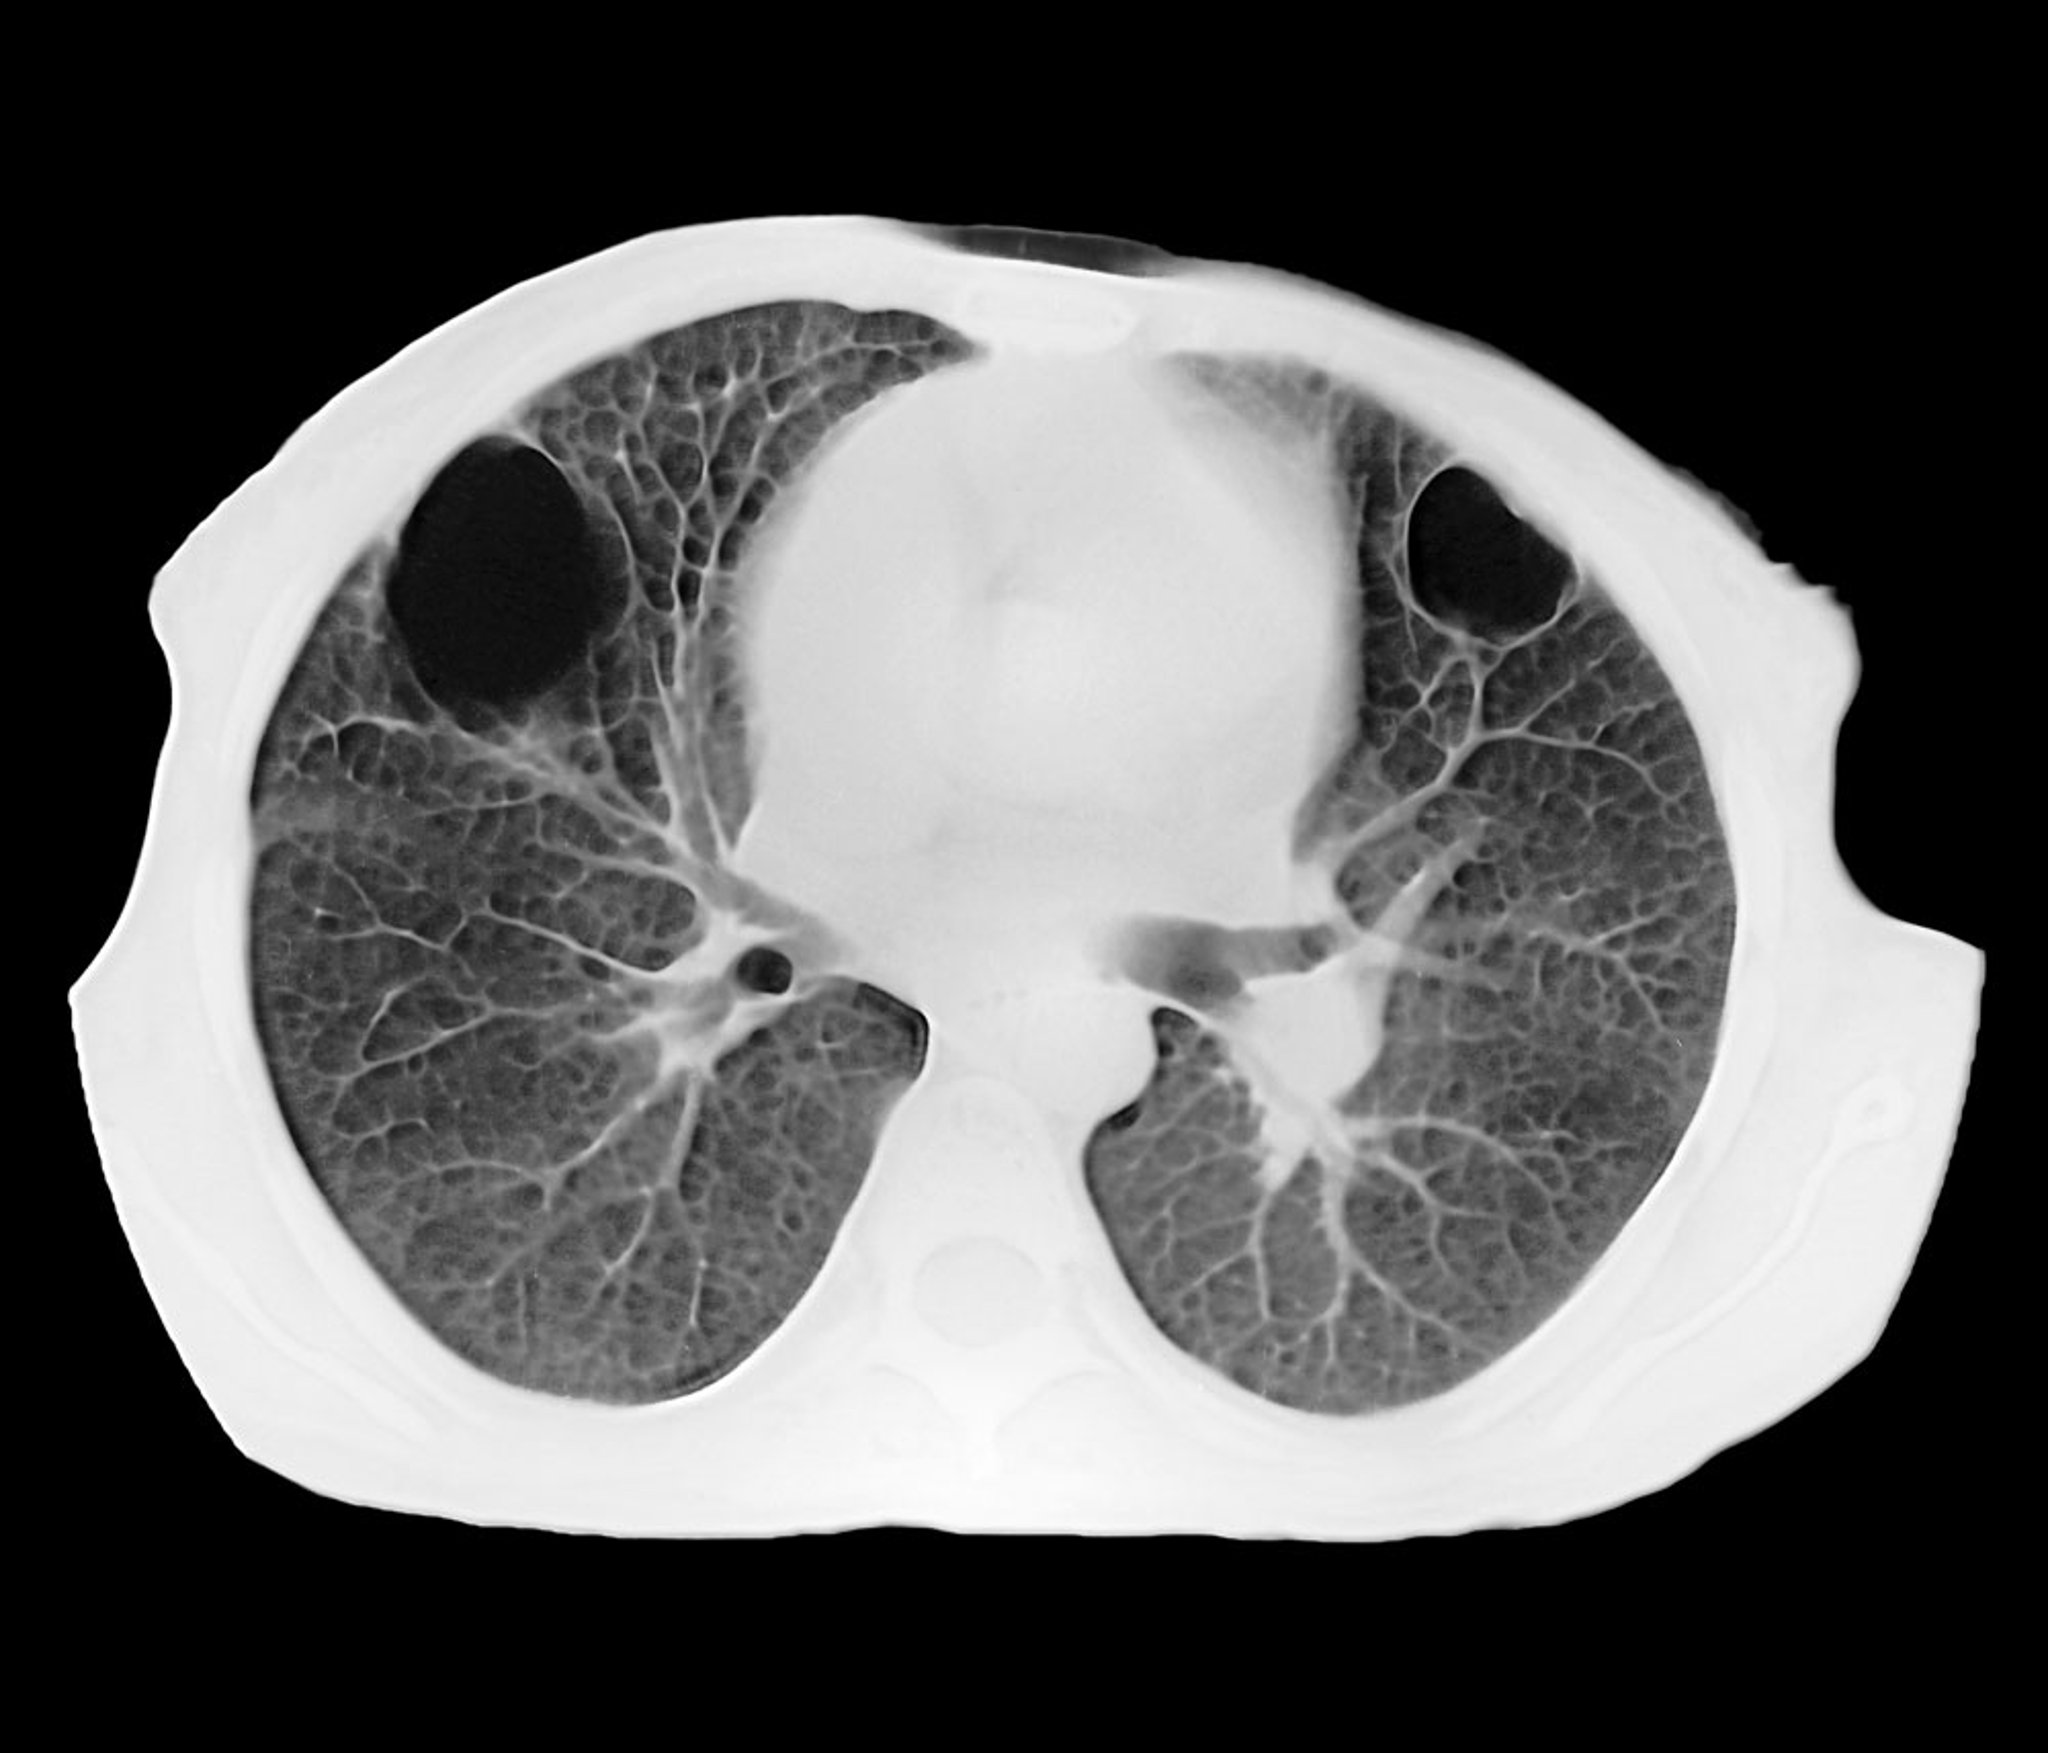

Abscesso pulmonar (TC)

Esta TC axial mostra 2 abscessos pulmonares parenquimatosos bem delimitados nos lobos anterior direito e esquerdo. O interior preto corresponde a um acúmulo de pus.